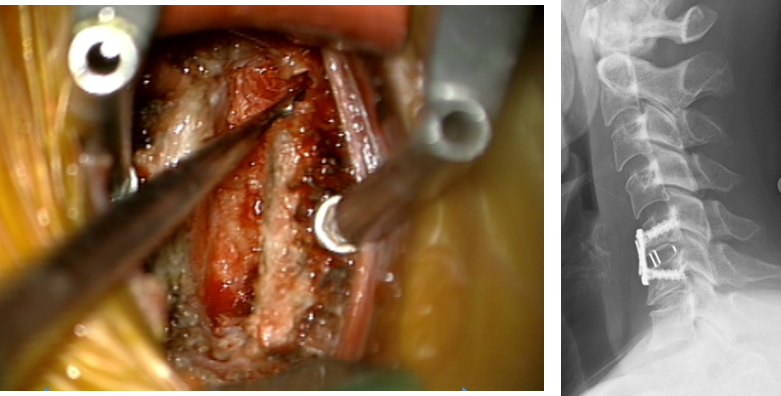

頚椎症スレ

酷くて困る

手術すれば大丈夫、怖くないよ( ・∀・)